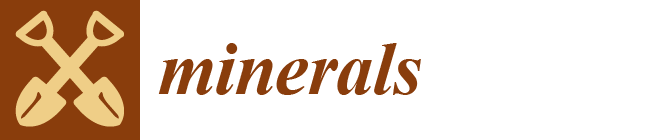

3.2. Osteopontin

3.3. Vascular Endothelial Growth Factor (VEGF)